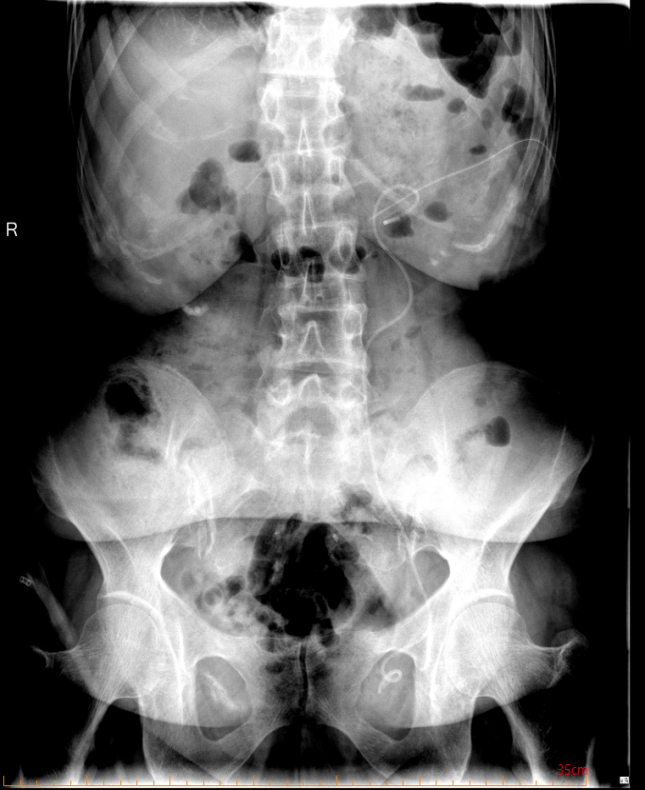

患者中年女性,約1年前曾因雙側(cè)腎結(jié)石,右輸尿管結(jié)石行體外碎石治療,治療后未復(fù)查,去年年底查體發(fā)現(xiàn)雙腎結(jié)石及右側(cè)輸尿管結(jié)石,因右輸尿管扭曲梗阻嚴(yán)重于我院行腹腔鏡下右側(cè)輸尿管切開取石術(shù),本次為處理左側(cè)腎結(jié)石第2次入院,入院后復(fù)查CT如下:

圖片